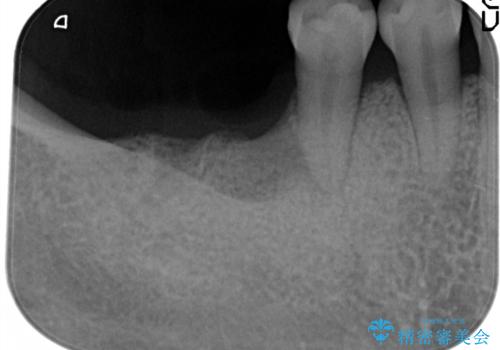

- 奥歯が破折していたため、抜歯を行ったあとインプラントを埋入して咬合回復を行っております。

インプラント埋入時に骨が足りない場合にはインプラント埋入時に骨増生を行います